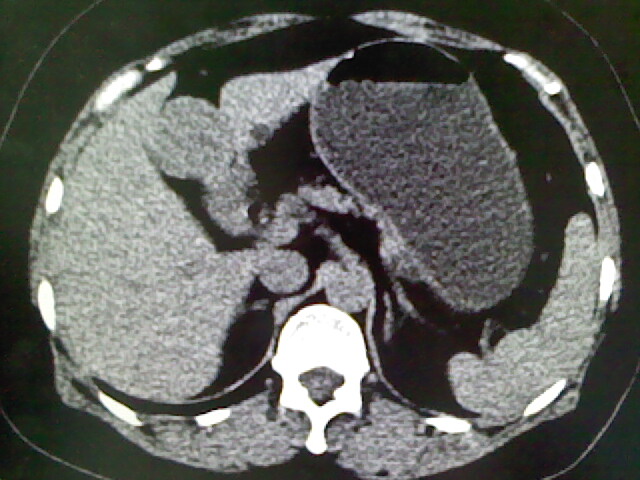

以下是引用卜一在2009-4-2 13:26:00的发言:[br]胆囊颈部结石伴胆囊炎!另:建议增强,待除外肝内占位及胆囊占位!

以下是引用liaoqiang在2009-4-2 16:23:00的发言:[br]胆囊是否切除?胆囊颈区致密影考虑金属夹?结石?肝脏右叶低密度影,考虑增强。